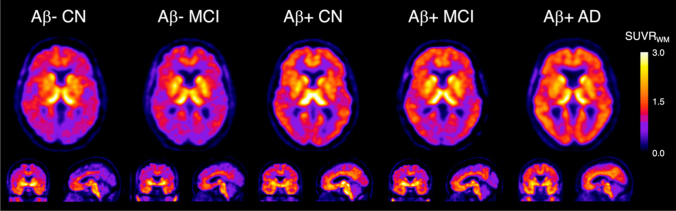

In vitro autoradiography of postmortem experiments showed that [18F]SMBT-1 possessed a higher specific binding in brain sections of patients with AD than in the control group, and this result was reproduced by MAO-B immunohistochemistry [95]. In a preliminary clinical study, [18F]SMBT-1 binding highly correlated with amyloid but not with tau burden. Patients positive for Aβ with normal cognition and those with MCI presented a significantly higher regional binding of [18F]SMBT-1 (Fig. 5, [96]). Additionally, Chatterjee et al. have demonstrated that plasma GFAP was associated with regional [18F]SMBT-1 signaling in patients with AD [97].

Fig. 5.

[18F]SMBT-1 PET images in AD and cognitive normal subject. This research was originally published in JNM. Villemagne VL, Harada R, Dore V, Furumoto S, Mulligan R, Kudo Y, et al. Assessing Reactive Astrogliosis with 18F-SMBT-1 Across the Alzheimer Disease Spectrum. J Nucl Med. 2022;63:1560-9.

© SNMMI